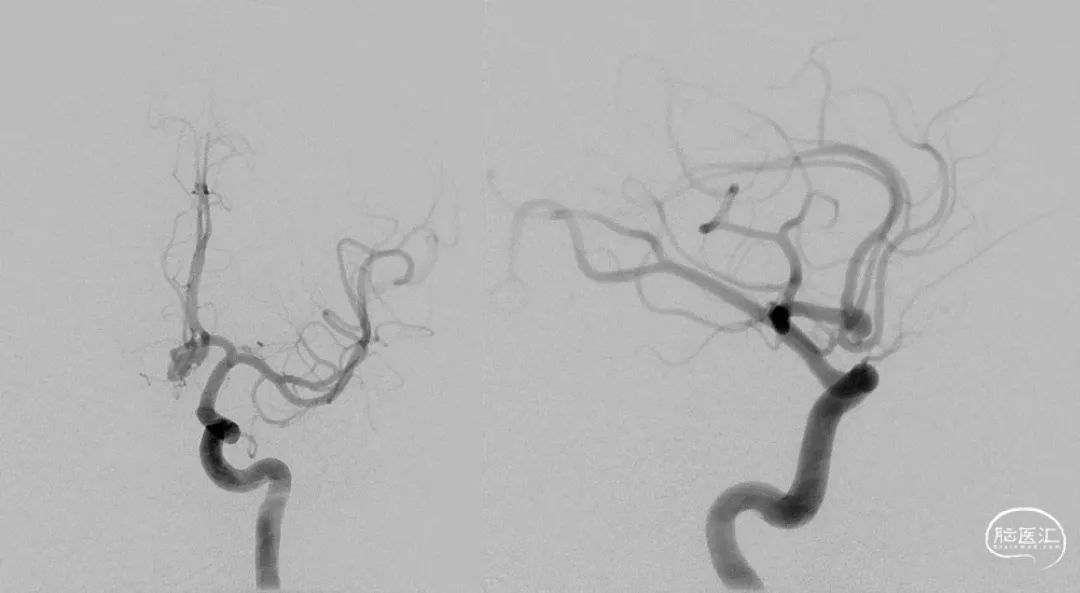

DSA提示左侧前交通动脉瘤大小4.5×4.7mm,宽颈3.4mm,瘤顶有一子囊。

入院后与家属沟通,完善检查后,先行脑血管造影,确定了动脉瘤的具体情况后,再次与家属沟通,患者颈内动脉比较迂曲,通路有一定的困难,可以行开颅手术夹闭术,也可以行血管内介入支架辅助动脉瘤栓塞术。家属一致要求行介入治疗,故全麻后,拟行栓塞治疗。

以220cm泥鳅导丝辅助上全新的6F/105cm Heralder®DA远端通路导引导管,泥鳅导丝置于颈内动脉海绵窦段提供适度的引导,然后Heralder®DA很轻松的进入颈内动脉岩段,显示了此款导管通过性能非常好。

支架导管到位手推造影。